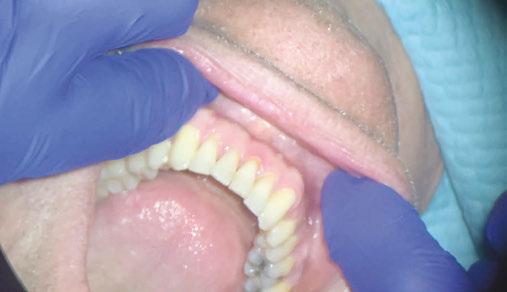

Figure 2: Initial lower occlusal

This case involves a 13-year-old female patient with a complex malocclusion that includes multiple dental and skeletal issues. During the initial consultation, clinical evaluation showed severe maxillary crowding along with generalized spacing in the mandibular arch. The patient’s occlusal relationships were asymmetric, with a Class I molar relationship on the right side and a Class II molar relationship on the left. Notably, an anterior crossbite was observed, further complicated by a narrow, V-shaped maxillary arch — a common presentation that often exacerbates anterior-posterior discrepancies and limits functional occlusion. The patient also demonstrated poor oral hygiene, which is a key indicator of an indirect bonding system that does not reduce excess flash. ODB is superior in flash reduction, by being able to remove excess adhesive from three sides of the bracket instead of competitors who only remove adhesive from one side of the bracket. The presence of adhesive around brackets contributes to surface roughness which leads to plaque accumulation.1 Flash reduction will be very important for every patient’s orthodontic success (Figures 1-3).